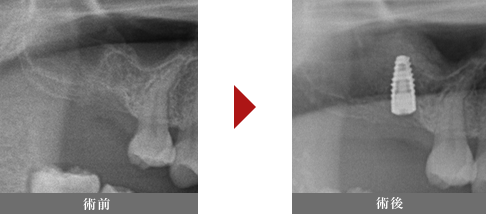

サイナスリフト法 サイナスリフトとは

上顎洞という副鼻腔のうちの一つ、鼻と繋がってる空洞の部分の粘膜を横から窓開けをして持ち上げ、 骨補填材(骨になる材料)を補填する処置です。 インプラント関連手術の中では難易度が高く道内でも手術可能な歯科医師はわずかですが、 当院では日常的に行っている治療方法です。

難易度が高いため、札幌市を中心に出張手術の依頼をよくいただく手術です。 補填する人工骨や自家骨にもよりますが、術後半年〜8ヶ月にインプラントを埋入することとなります。

症例

40代女性

治療回数:1回

治療費:インプラント埋入費用(通常の治療費)+人工骨材料代(50,000円〜)

リスク:上顎洞の感染